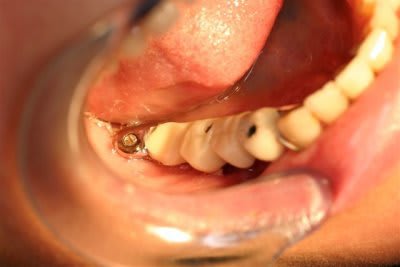

4 Utilisation d'un implant à plaque.

La vis d'ostéosyntèse impossible à dévisser a dû être coupée.